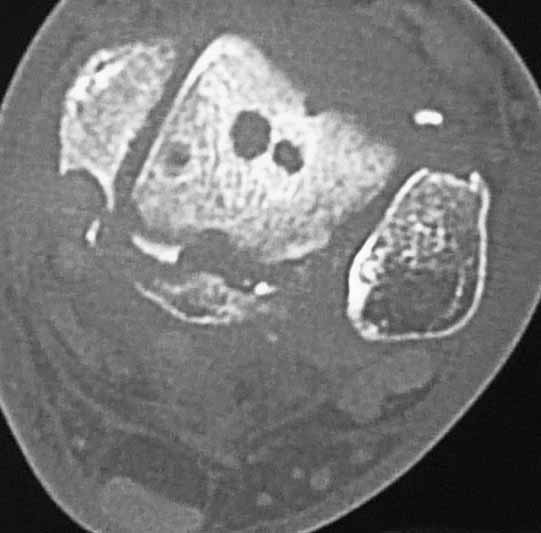

Уважаемые коллеги. Не так давно на форуме коротко обсуждались возможные последствия трансартикулярной фиксации голеностопного сустава при переломовывихах лодыжек.

На днях довелось увидеть КТ после удаления спиц. Картинки наглядные и, практически, не нуждаются в комментариях. Одна из спиц, кстати, проходила через фрагмент заднего края.

Картинки наглядные и, практически, не нуждаются в комментариях. Одна из спиц, кстати, проходила через фрагмент заднего края

Снимки являются доказательством важности защиты суставного хряща от грубой интервенции, и особенно от тех неудачных многочисленных попыток фиксации спицами, когда спицы оставляют на поверхности сустава непоправимые следы. Понятно, что повреждение целости хряща приводит к развитию хондролизиса, артрозу и т.д....

Понятно, огромные “дырки” в суставе не от хорошей жизни, хотя на самом деле “увеличенная картина” на КТ срезах может оказаться банальным проколом от 1,2 или 2 мм спиц. Большие неприятности, когда спицы находятся долго, и когда лизис вокруг спицы принимает большие размеры. А так - не стал бы драматизировать единичные спицы, установленные на короткое время, потому что такие “интервенции” сустава у большинства больных проходят без клинических проявлений.